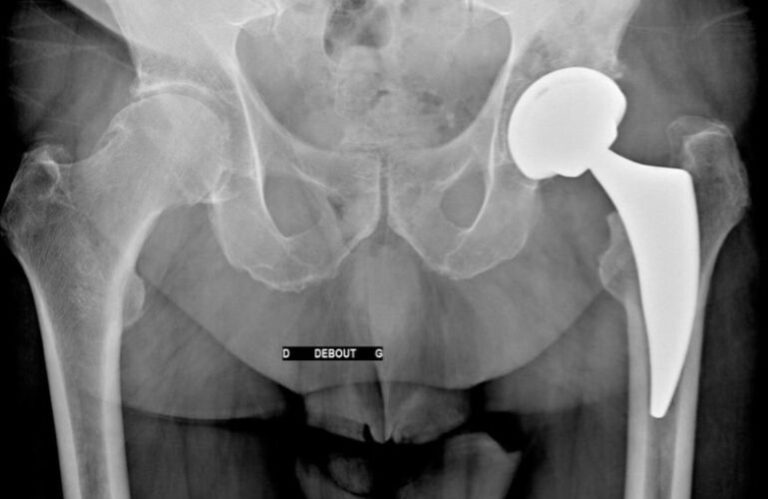

- Plus tardivement : l’arthrose précoce : c’est une usure du cartilage accélérée par le sport de haut niveau ou des traumatismes répétés. Le développement de l’arthrose est favorisé par les activités traumatisantes répétées. Ex: arthrose des hanches et des genoux chez les footballeurs et les rugbymen pro.